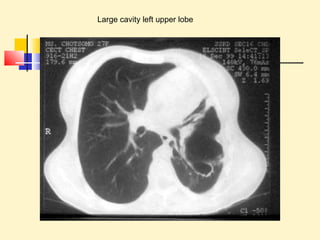

Large cavity left upper lobe